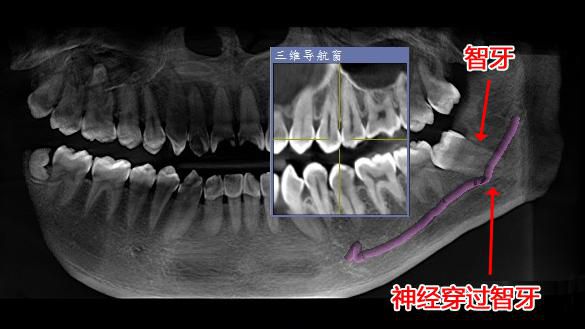

△經西諾德3D口腔全景CT檢查發現神經穿過智牙。

爲預防神經損傷,拔除智牙前,有必要先通過口腔全景CT了解牙根與下颌神經管的關系。如盲目操作易損傷神經,出現下唇及颏部皮膚不完全性麻木或兼有燒灼、刺痛、蟻走等異常感。